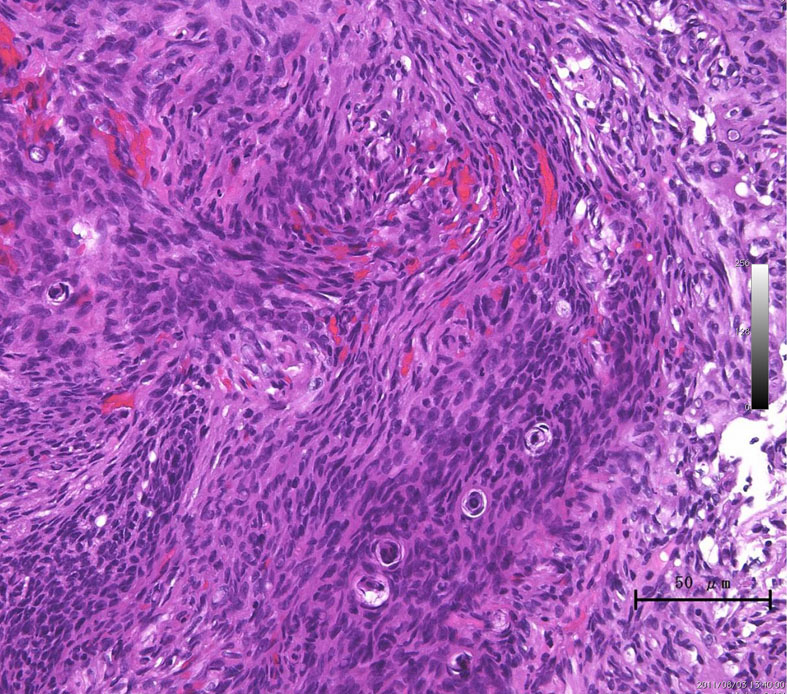

atypical meningioma WHO grade 2(長嶋和郎先生の病理教室)

高齢者の後頭窩 (ptrous ridge) にみられた大きな髄膜腫でした。meningiomaと考えられますが、whorl patternやmeningothelial featureなど特徴的なpatternが見られずpattern lessと見做されます。さらに、腫大しchromatinに富む核が見られ、異型細胞と考えられます。

EMAが陽性となることでmeningiomaが示唆されます(左:EMA染色 x200x)。腫瘍の一部でcollagen fiberの多い組織に移行し、核の消失を伴う壊死性変化を示す部位が見られます。

腫瘍の周辺部にonion bulb構造 (→)が見られ、meningiomaの診断が妥当です(左)。細胞核の異型性がありMIB-1 indexが10%と高値であり(右)、atypical meningiomaです。